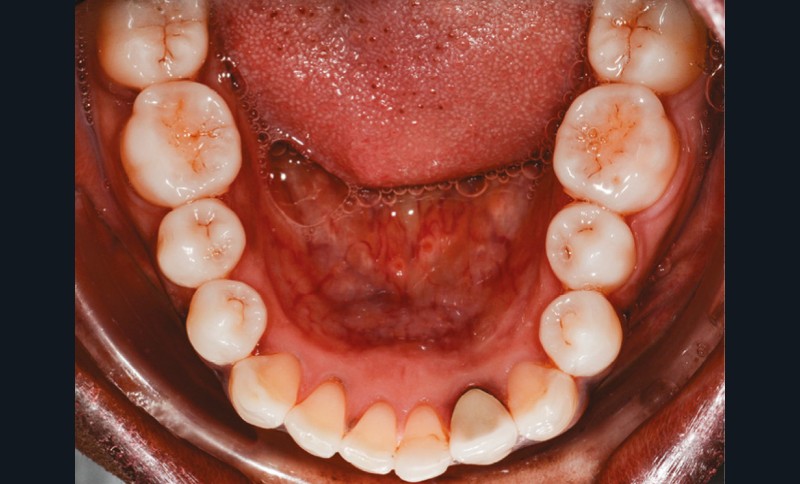

L’observation clinique après traitement parodontal initial révèle, au niveau interarcade, des rapports de classe I molaire bilatéraux associés à des rapports de bout à bout incisif. Dans la dimension verticale, elle présente une légère infraclusion antérieure. On ne note pas d’anomalie de la dimension transversale (fig. 3 à 5). À l’examen intra-arcade, on constate des diastèmes maxillaires interincisifs (1 mm), en distal de 13 (0,5 mm) et de 24 (1 mm) ainsi que des malpositions unitaires (linguoversion de 12, rotation mésio-vestibulaire disto-linguale de 24). À la mandibule, on observe une couronne céramométallique au niveau de 32 plus large de 1,5 mm que les autres incisives ainsi qu’une rotation mésio- linguale de 35 (fig. 6 à 8). En diduction, on note une interférence au niveau de 24.